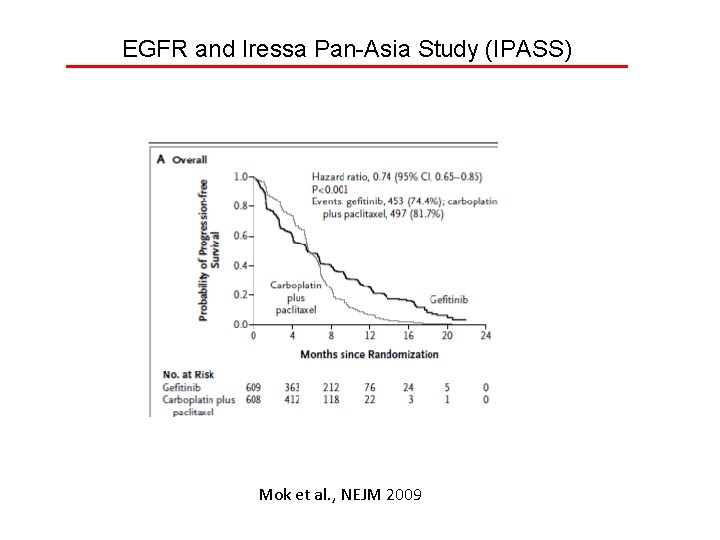

EGFR and Iressa Pan-Asia Study (IPASS) Mok et al. , NEJM 2009